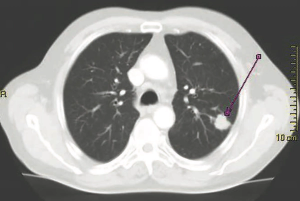

Five notable abstracts from the 2019 World Conference on Lung Cancer (WCLC).